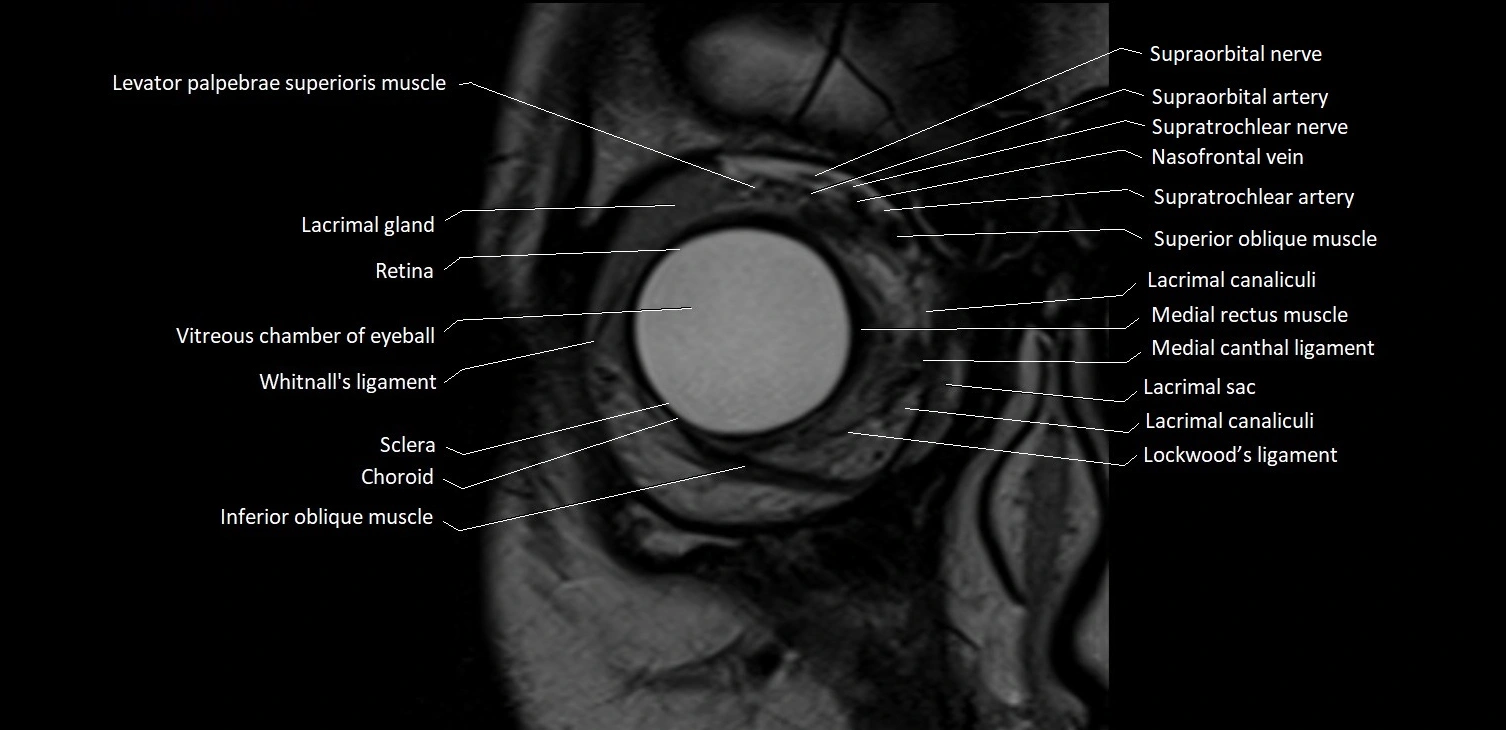

- Choroid

- Inferior oblique muscle

- Lacrimal canaliculi

- Lacrimal gland

- Levator palpebrae superioris muscle

- Lockwood’s ligament

- Medial canthal ligament

- Medial rectus muscle

- Nasofrontal vein

- Retina

- Sclera

- Superior oblique muscle

- Supraorbital artery

- Supraorbital nerve

- Supratrochlear artery

- Supratrochlear nerve

- Vitreous chamber of eyeball

- Whitnall's ligament